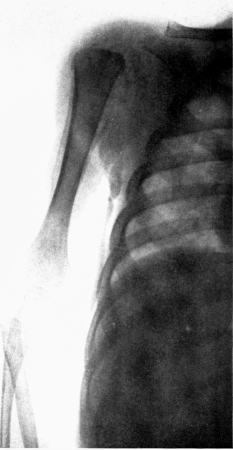

| 18. | Infant with marked scurvy. Characteristic position | 198 |

| 19. | Scorbutic beading of ribs. Roentgenogram | 198 |